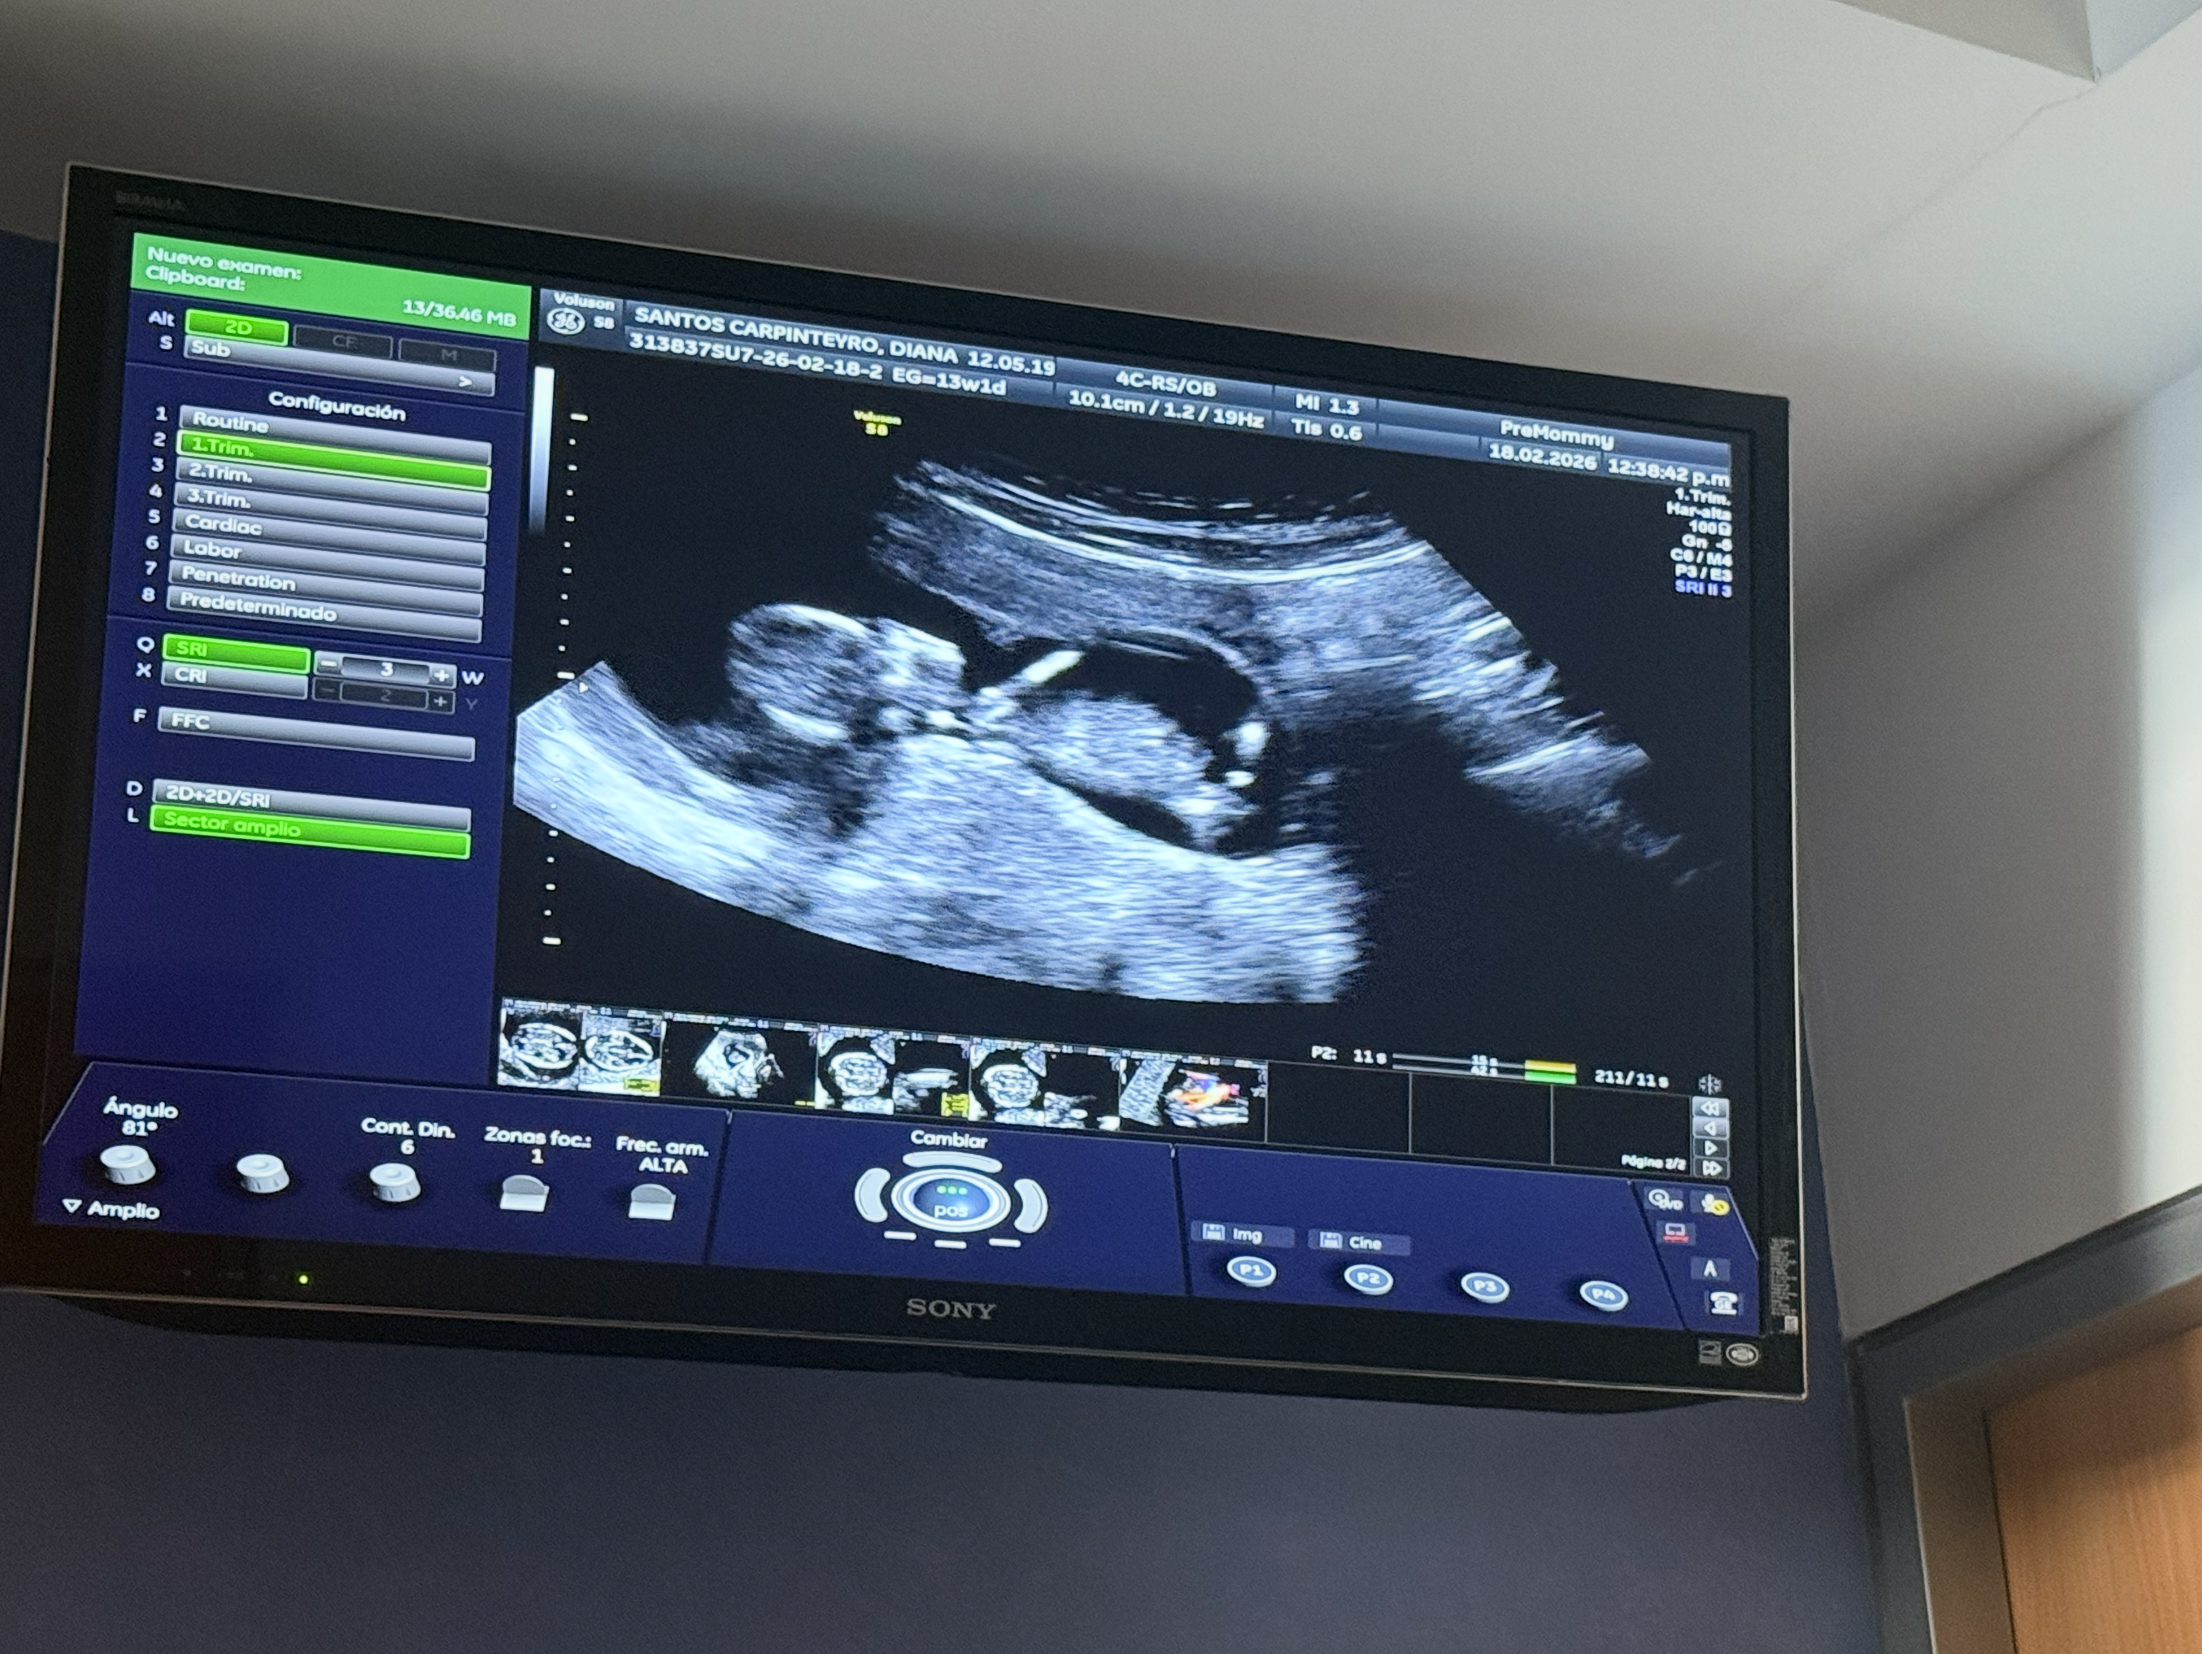

Hola de nuevo, bebé!

Hoy te vimos otra vez, nos dijeron que estás muy sano! También el doctor ya sabe qué eres pero le pedimos guardar el secreto